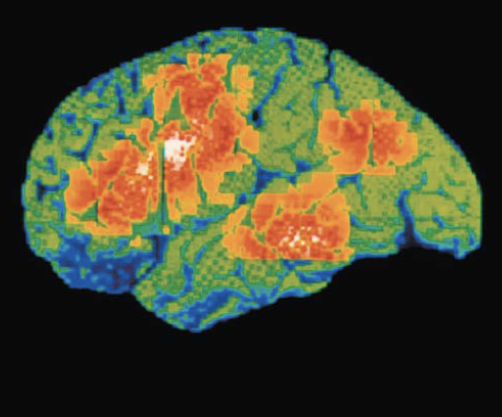

Functional imaging (PET and MRI) of brain show specific motor and sensory functions are located in discrete cortical areas called domains

Conscious behavior involves entire cortex in one way or another

Multimodal association areas

Receive inputs from multiple sensory areas

Send outputs to multiple areas

Allows us to give meaning to information received, store in memory, tie to previous experience, and decide on actions

Sensations, thoughts, emotions become conscious: makes us who we are

Broadly divided into three parts: anterior association area, posterior association area,and limbic association area